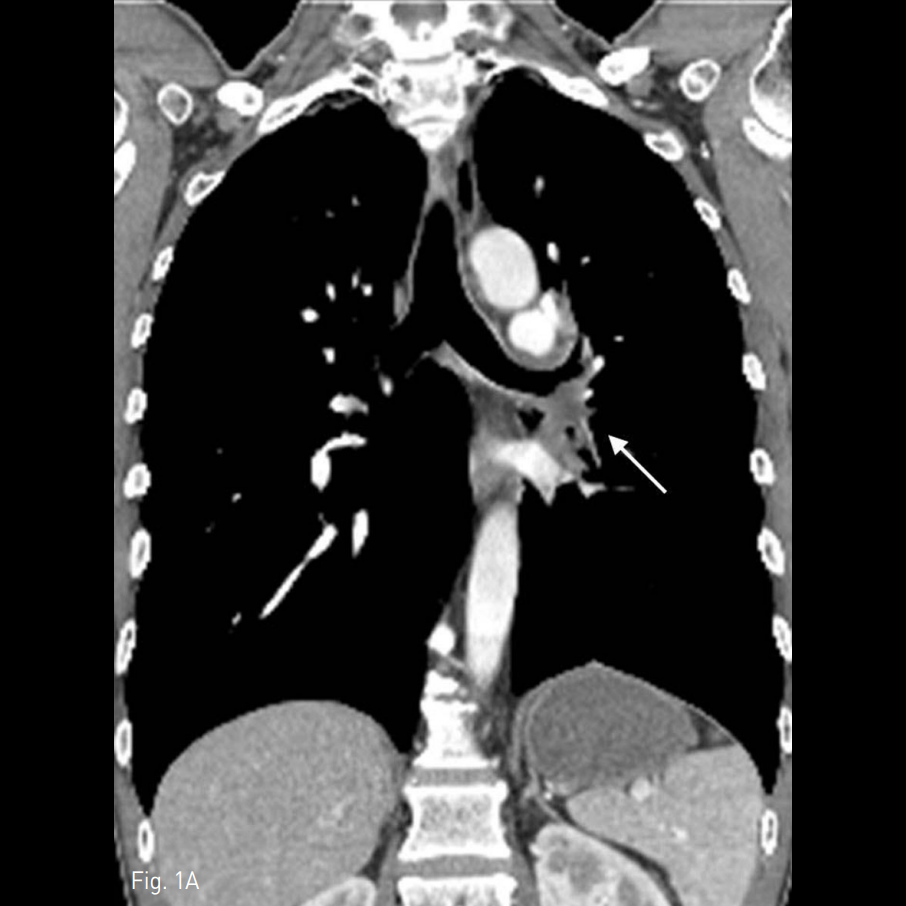

A. The post-contrast chest CT image shows diffuse wall thickening of the left lower bronchus (white arrow).

B. The high resolution chest CTimage reveals multifocal areas of ground glass opacity and consolidation in the right middle lobe and left low er lobe suggesting aspirated blood.